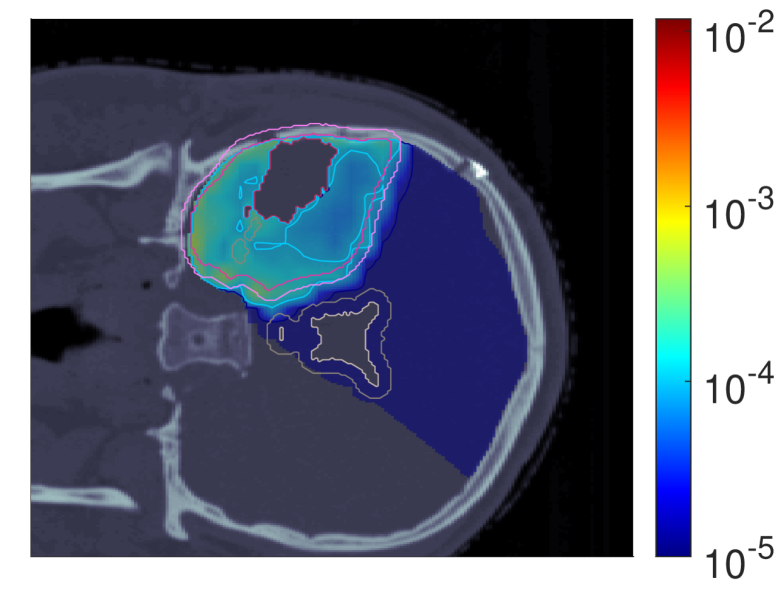

III.A.2 Dose-averaged linear energy transfer ldl_{d}

In light of the dose distribution changes and the interdependency between dose and dose-averaged LET, we can identify patterns in the slice images with the optimal dose-averaged LET distributions shown in Figure 5.

NTCP30 %NTCP\approx{$30\text{\,}\mathrm{\char 37\relax}$} NTCP20 %NTCP\approx{$20\text{\,}\mathrm{\char 37\relax}$} NTCP10 %NTCP\approx{$10\text{\,}\mathrm{\char 37\relax}$}

ldl_{d} (NTCPp)(NTCP_{p})

Refer to caption Refer to caption Refer to caption

ldl_{d} (LSEp~)(LSE_{\tilde{p}})

ldl_{d} (H~p)(\tilde{H}_{p})

ldl_{d} (H~p~)(\tilde{H}_{\tilde{p}})

Figure 5: Optimal slice images of the dose-averaged linear energy transfer ldl_{d} (in keV/μ\boldsymbol{\mu}m) for NTCPpNTCP_{p}, LSEp~LSE_{\tilde{p}}, H~p\tilde{H}_{p} and H~p~\tilde{H}_{\tilde{p}} at different NTCP levels. The shifts in ldl_{d} coincide with those observed on the slice images for dRBE,fxd_{RBE,fx}, i.e., there seems to be a trade-off between dRBE,fxd_{RBE,fx} and ldl_{d} that is consistent with the mathematical structure of the POLO model. As a result, the ldl_{d} slice images for NTCPpNTCP_{p} and H~p\tilde{H}_{p} are almost equivalent, while LSEp~LSE_{\tilde{p}} and H~p~\tilde{H}_{\tilde{p}} differ. For the latter two objective functions, the shift of dRBE,fxd_{RBE,fx} outside the target volume appears to be crucial, or, respectively, no shift of ldl_{d} is necessary due to the strength of the reduction of dRBE,fxd_{RBE,fx}.

First, we note that ldl_{d} hotspots do not manifest in the high dose regions – this would be a risk driver because of the product term in the POLO model from Section II.A. Generally, some trade-off between dRBE,fxd_{RBE,fx} and ldl_{d} is evident, where the optimizer allows for higher values of ldl_{d} when dRBE,fxd_{RBE,fx} has been sufficiently reduced, and vice versa.

For NTCPpNTCP_{p}, the slight reduction of dRBE,fxd_{RBE,fx} outside the target volume coincides with a redistribution of ldl_{d}: higher values in the target volume are prevented, and instead induced along the margins of the PTV. Once again, H~p\tilde{H}_{p} behaves almost identically. Following the dose/LET trade-off, the almost unchanged values for LSEp~LSE_{\tilde{p}} can also be explained: LSEp~LSE_{\tilde{p}} minimally reduces dRBE,fxd_{RBE,fx} in the region of overlap with the VS, meaning that high ldl_{d} values there would be detrimental to the outcome prediction. Consequently, ldl_{d} could only approach the “dose gap” that opens up within the target volume, or remain constant while the shifts in the dose distribution account for the reduction in NTCP.

Finally, for H~p~\tilde{H}_{\tilde{p}}, we observe a sharp envelopment of the lower side of the PTV margin, consistent with the fall-off in dRBE,fxd_{RBE,fx} there. At an NTCP level of 10 %10\text{\,}\mathrm{\char 37\relax}, the high ldl_{d} region has virtually manifested itself with hot spots partially overlapping the VS. However, revisiting the slice image for dRBE,fxd_{RBE,fx}, this is not surprising, as in addition to the lower values in the target volume, the dissipation of dRBE,fxd_{RBE,fx} to the outside is only enhanced towards the upper end, leaving space for the ldl_{d} band on the lower end, between the PTV margin and the VS.

Again, we can confirm the slice images by the LET-volume histograms (LET-VHs) from Figure 6. For NTCPpNTCP_{p} and H~p\tilde{H}_{p}, the values decrease with lower NTCP for all VOIs. LSEp~LSE_{\tilde{p}} almost does not change the distributions, only a slight increase at the left margin of the target volume is visible both in the slice images and in the respective LET-VH curves. Meanwhile, H~p~\tilde{H}_{\tilde{p}} reduces the values in all VOIs, just as NTCPpNTCP_{p} and H~p\tilde{H}_{p}, but in contrast, for the VS, the lower range is more attenuated and the upper range is enriched due to the redistribution along the PTV margin.